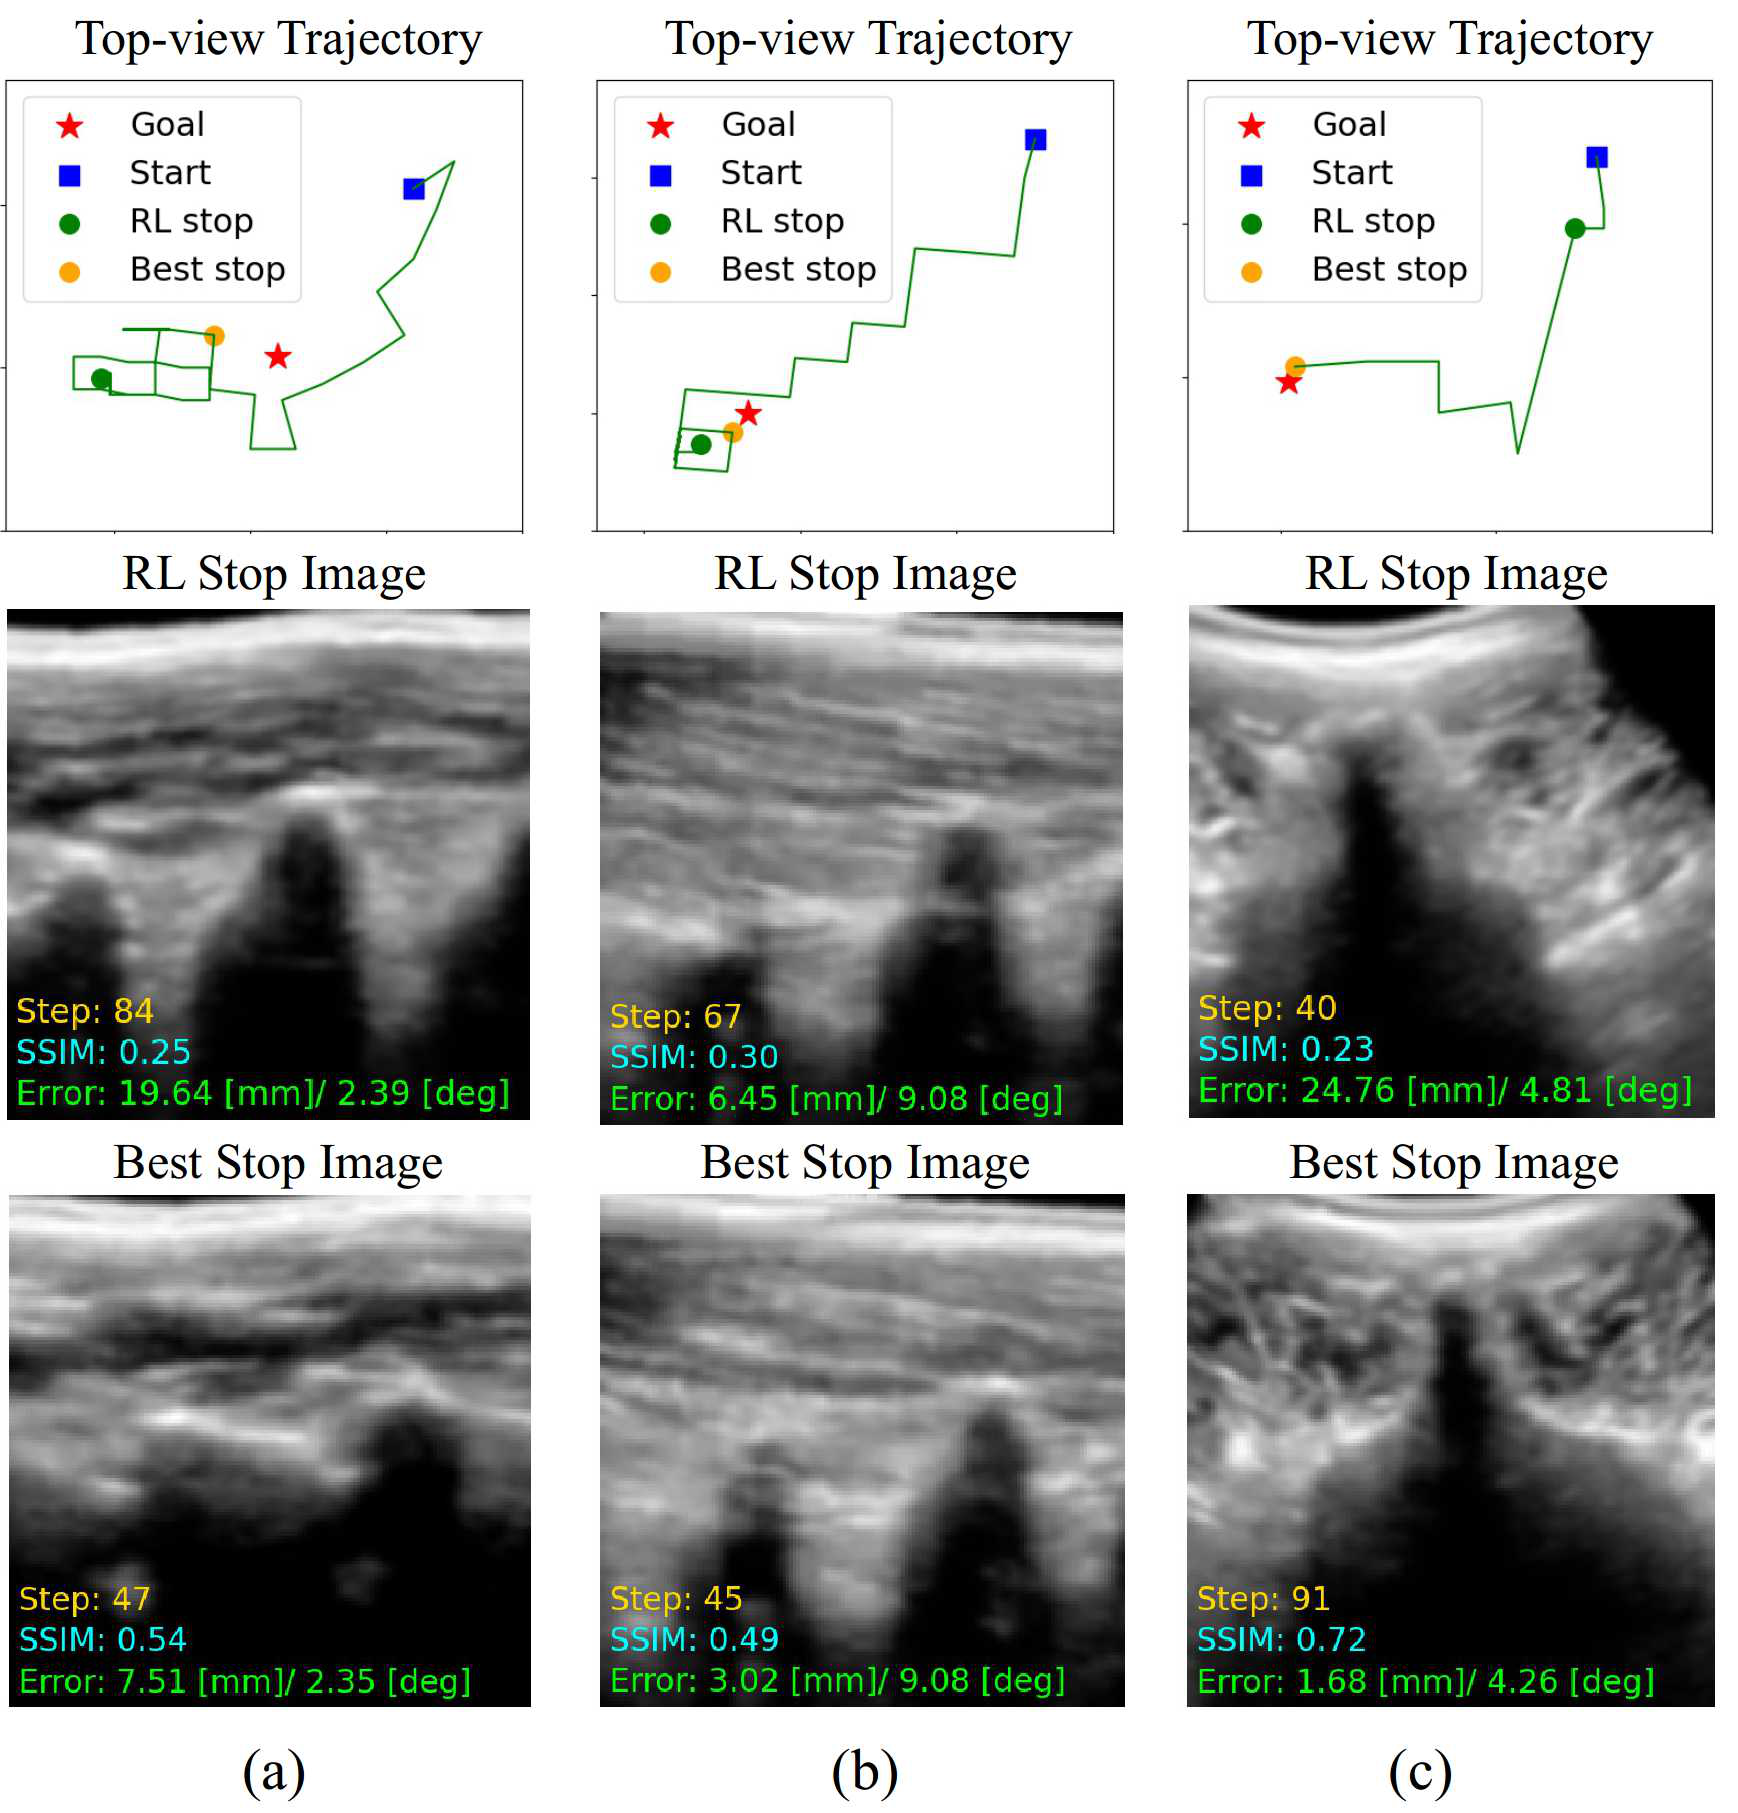

We further investigate the effectiveness of the dual-agent collaborative navigation through qualitative analysis. As shown in Fig. 12, the standard view acquisition results of the “RL+ASR” and “RL+ASR+DL” methods are compared on example test cases. It can be observed in Fig. 12(a) that the “RL+ASR” agent takes a zig-zag path toward the PSL view in the first 40similar-toabsent40\sim 40 steps, and then moves aways from the goal and terminates the navigation at step 848484, ending up with a pose error of 19.64mm/2.3919.64𝑚𝑚superscript2.3919.64mm/2.39^{\circ} and a low SSIM of 0.250.250.25. While the “RL+ASR+DL” stops at step 474747, with a pose error of 7.51mm/2.357.51𝑚𝑚superscript2.357.51mm/2.35^{\circ} and an SSIM of 0.540.540.54, showing that using the standard view recognition results for active termination can effectively improve the navigation performance. For the PSAP view acquisition, as shown in Fig. 12(b), the “RL+ASR” agent also gradually approaches the goal at first, but takes some wrong actions in the last 202020 steps and ends up with a slight deviation from the goal (6.45mm/9.086.45𝑚𝑚superscript9.086.45mm/9.08^{\circ}). By applying the dual-agent collaboration navigation method, the stopping position is closer to goal (3.02mm/9.083.02𝑚𝑚superscript9.083.02mm/9.08^{\circ}), and the SSIM is also increased from 0.300.300.30 to 0.490.490.49. As shown in Fig. 12(c), during the navigation toward TSP view, the “RL+ASR” agent gets trapped around the initial position and stops at step 404040 with a large pose error of 24.76mm/4.8124.76𝑚𝑚superscript4.8124.76mm/4.81^{\circ}. In contrast, the “RL+ASR+DL” agent makes an exploration and begins a new round of search, and successfully reaches the goal at step 919191, with a high accuracy of 1.68mm/4.261.68𝑚𝑚superscript4.261.68mm/4.26^{\circ} and an SSIM of 0.720.720.72. This is because the proposed dual-agent framework can mimic the behavior of a sonographer to randomly reposition the probe on the patient multiple times. As a result, it can escape from bad initial positions to better search for the target anatomy and efficiently navigate the probe toward the goal within the time limit.

Refer to caption

Figure 12: (a)-(c) illustrate the PSL, PSAP, and TSP view acquisitions by the “RL+ASR” and “RL+ASR+DL” methods on example test cases. The first line shows the top-view navigation trajectories toward each target standard view (green line), with the start and goal positions indicated by a blue square and a red star. The final stopping position of the RL agent (“RL stop”) and the best stop determined by dual-agent collaborative navigation (“best stop”) are indicated by green and orange balls, respectively. The next two lines show the final images acquired at the RL stop and the best stop, with the corresponding termination step (yellow), final SSIM (cyan) and pose error (green).